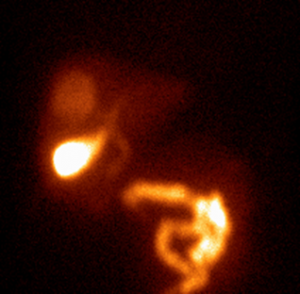

21.6.2.1. Meckel’s diverticule

In infants GI bleeding can also occur from the ectopic gastric mucosa in Meckel’s diverticulum. The diverticulum’s gastric mucosal membrane can be identified with 99mTc-pertechnetate scintigraphy. The isotope is accumulated in both normal and ectopic gastric mucosal membrane and the ectopic mucosa will appear as a circumscribed activity increase outside the stomach’s area. (Figure 21.)

21. Meckel-diverticulum with ectopic gastric mucosa. Anterior image was taken of the abdomen after 60 minutes of iv. injection of 99mTc-pertechnetate. In the right lower quadrant of the abdomen there is a pathological activity increase, while at the projection of the stomach the activity uptake is normal. (Urine activity is seen in the bladder.)